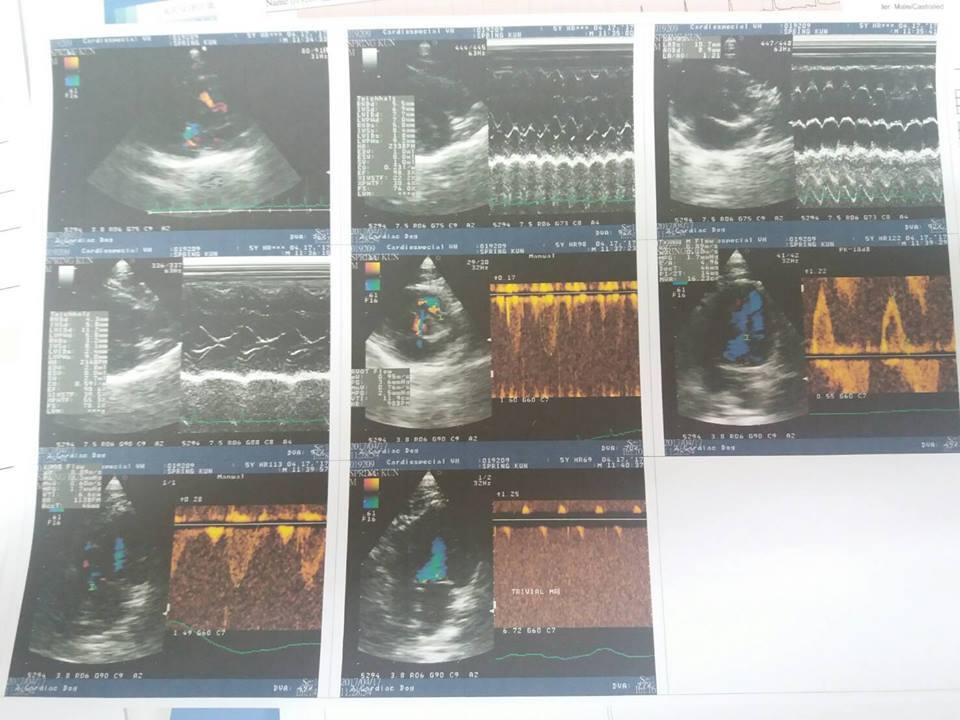

主題: 因心臟病須定期追蹤的溫泉君 申請者姓名: 臺北市支持流浪貓絕育計劃協會 花色: 申請日期: 2017-04-24 12:41:52 申請者部落格: 申請者臉書網址: 所在縣市/合作醫院: 台北市/其他院所醫助專案(醫院請先MAIL溝通) 治療費用: 11700元 需求人數: 13人 已結案 (2024-06-01 13:30:02) 報名人員: anne(已付款)、fotojo(已付款)、Joy Chang(已付款)、可樂 x5(已付款)、Stacey Ma x2(已付款)、洪郁茹(已付款)、阿芝、Ed Tsai(已付款)、陳昱先(已付款)、 候補人員: 動物病情說明: 溫泉君因為有心臟肥厚等問題,

導致心臟舒張和收縮的能力較差,

因此需要每天吃心臟藥

才能維持正常的心臟機能,

並定期每半年回診檢查心臟狀況是否穩定

4/17專心回診 溫泉君 3.95KG

【回診狀況】

今日血檢、X光、心電圖、超音波

溫泉君的心臟大小及厚度都有維持,目前狀況穩定

因此維持原先用藥劑量

今日血壓116-118

心跳190~200

血檢部分溫泉君的CRE同2/22,維持在1.9,為正常值但屬偏高

由於希望若溫泉君的心臟有栓塞的狀況可提早發現

但在院中較緊張,心跳很快

醫生希望溫泉的心臟在平時能在160以下,

超過160則需進一步思考是否多給予第二種心臟用藥

(能降低心跳但同時可能導致血壓較低)

因此需要每日量心跳以及呼吸,